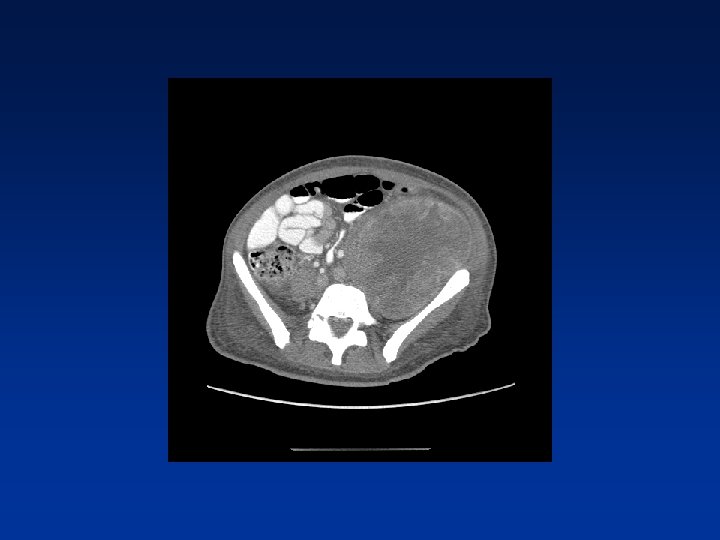

CASE